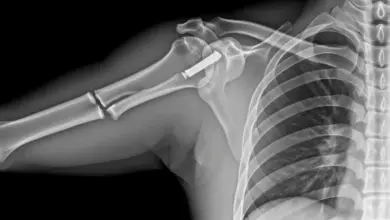

Clavícula Saltada É Normal? Quando Investigar

Ver uma “clavícula saltada” pode assustar. No consultório, muitos pacientes descrevem um osso mais alto perto do pescoço, uma “pontinha”…